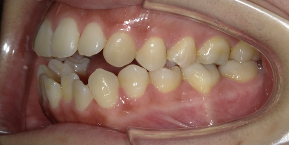

26歳女性のビフォーアフター

| 診断 | 空隙,叢生 |

| 治療方針 | 治療方針:前歯の咬合関係改善と空隙閉鎖を主な目的にて主にIPR(歯と歯の間をわずかに削合してスペースを獲得する方法)を組み込んだ動的矯正治療を行い、空隙、前歯咬合を改善後、保定を行う。臼歯部の咬合関係はプランの都合上維持することとした |

| 治療費 ※ | 69万8千円(診断、型取り、矯正中のメンテナンス、保定装置を含む料金) |

| 治療期間 | 1年8か月 |

| リスク | 1日20時間以上マウスピースを使用できない場合、歯が動かなかったり、想定しない誤差により不完全に終わる可能性がある。装着時や食事時に痛みを伴う。歯肉退縮や虫歯になるおそれがある。また、指導通りに装着できていない場合や適切なブラッシングが出来ていないとそのリスクが高くなる。歯根が短くなることがある。ごくまれに歯の神経が損傷してしまうことがある。過去にぶつけたり深い虫歯治療をしたことがあるとそのリスクはやや高くなる。矯正後には保定装置が必要。適切な使用ができない場合、後戻りの原因となる。将来的に歯並びが動いて再矯正が必要な場合がある。舌癖(舌で歯を押し出す癖)親知らずが正常に生えていない場合、その可能性がやや高くなる。 |